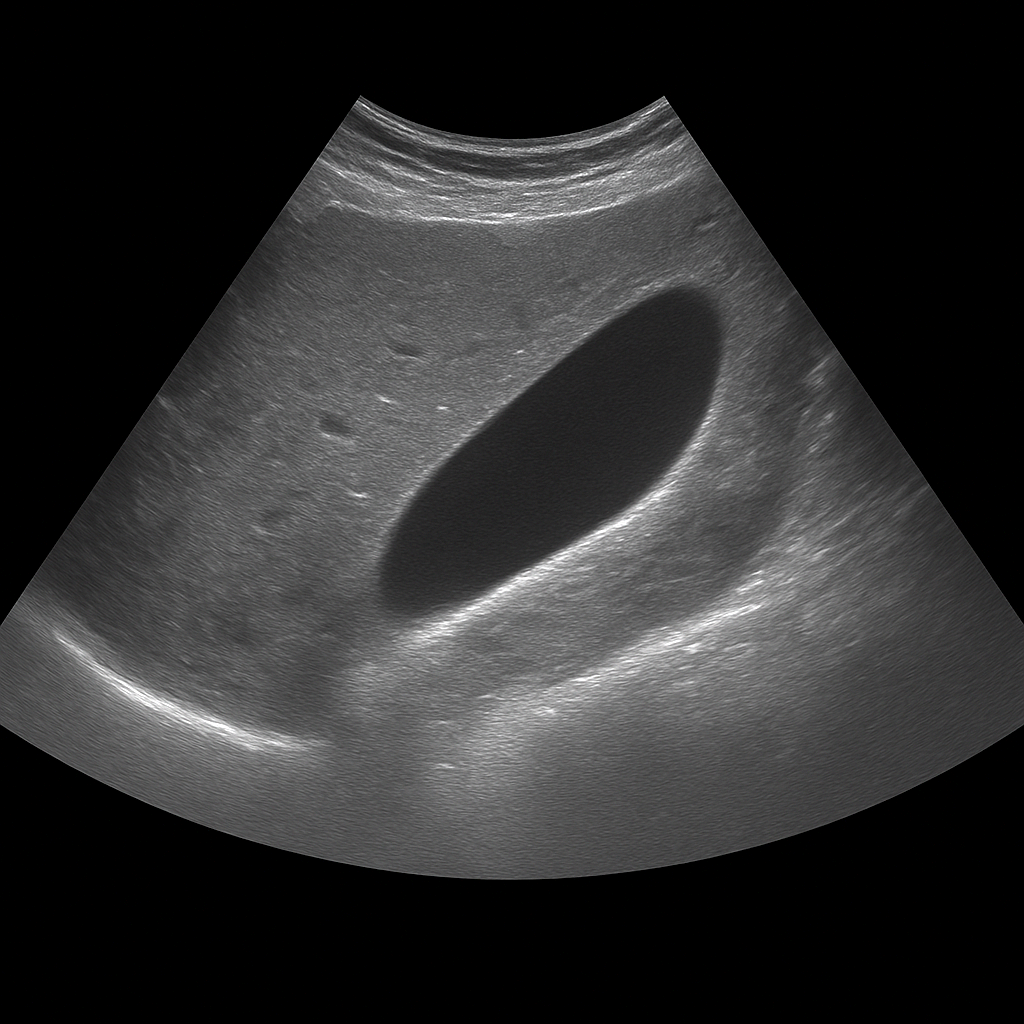

- Ultrasound of the abdomen shows the liver, gallbladder, pancreas, kidneys and other abdominal organs in real time.

- Recommended for abdominal pain, swelling, nausea or elevated liver values.

- Quick, painless and radiation-free examination of the internal organs of the abdomen.

- Written opinion and recommendation from a specialist doctor are included.